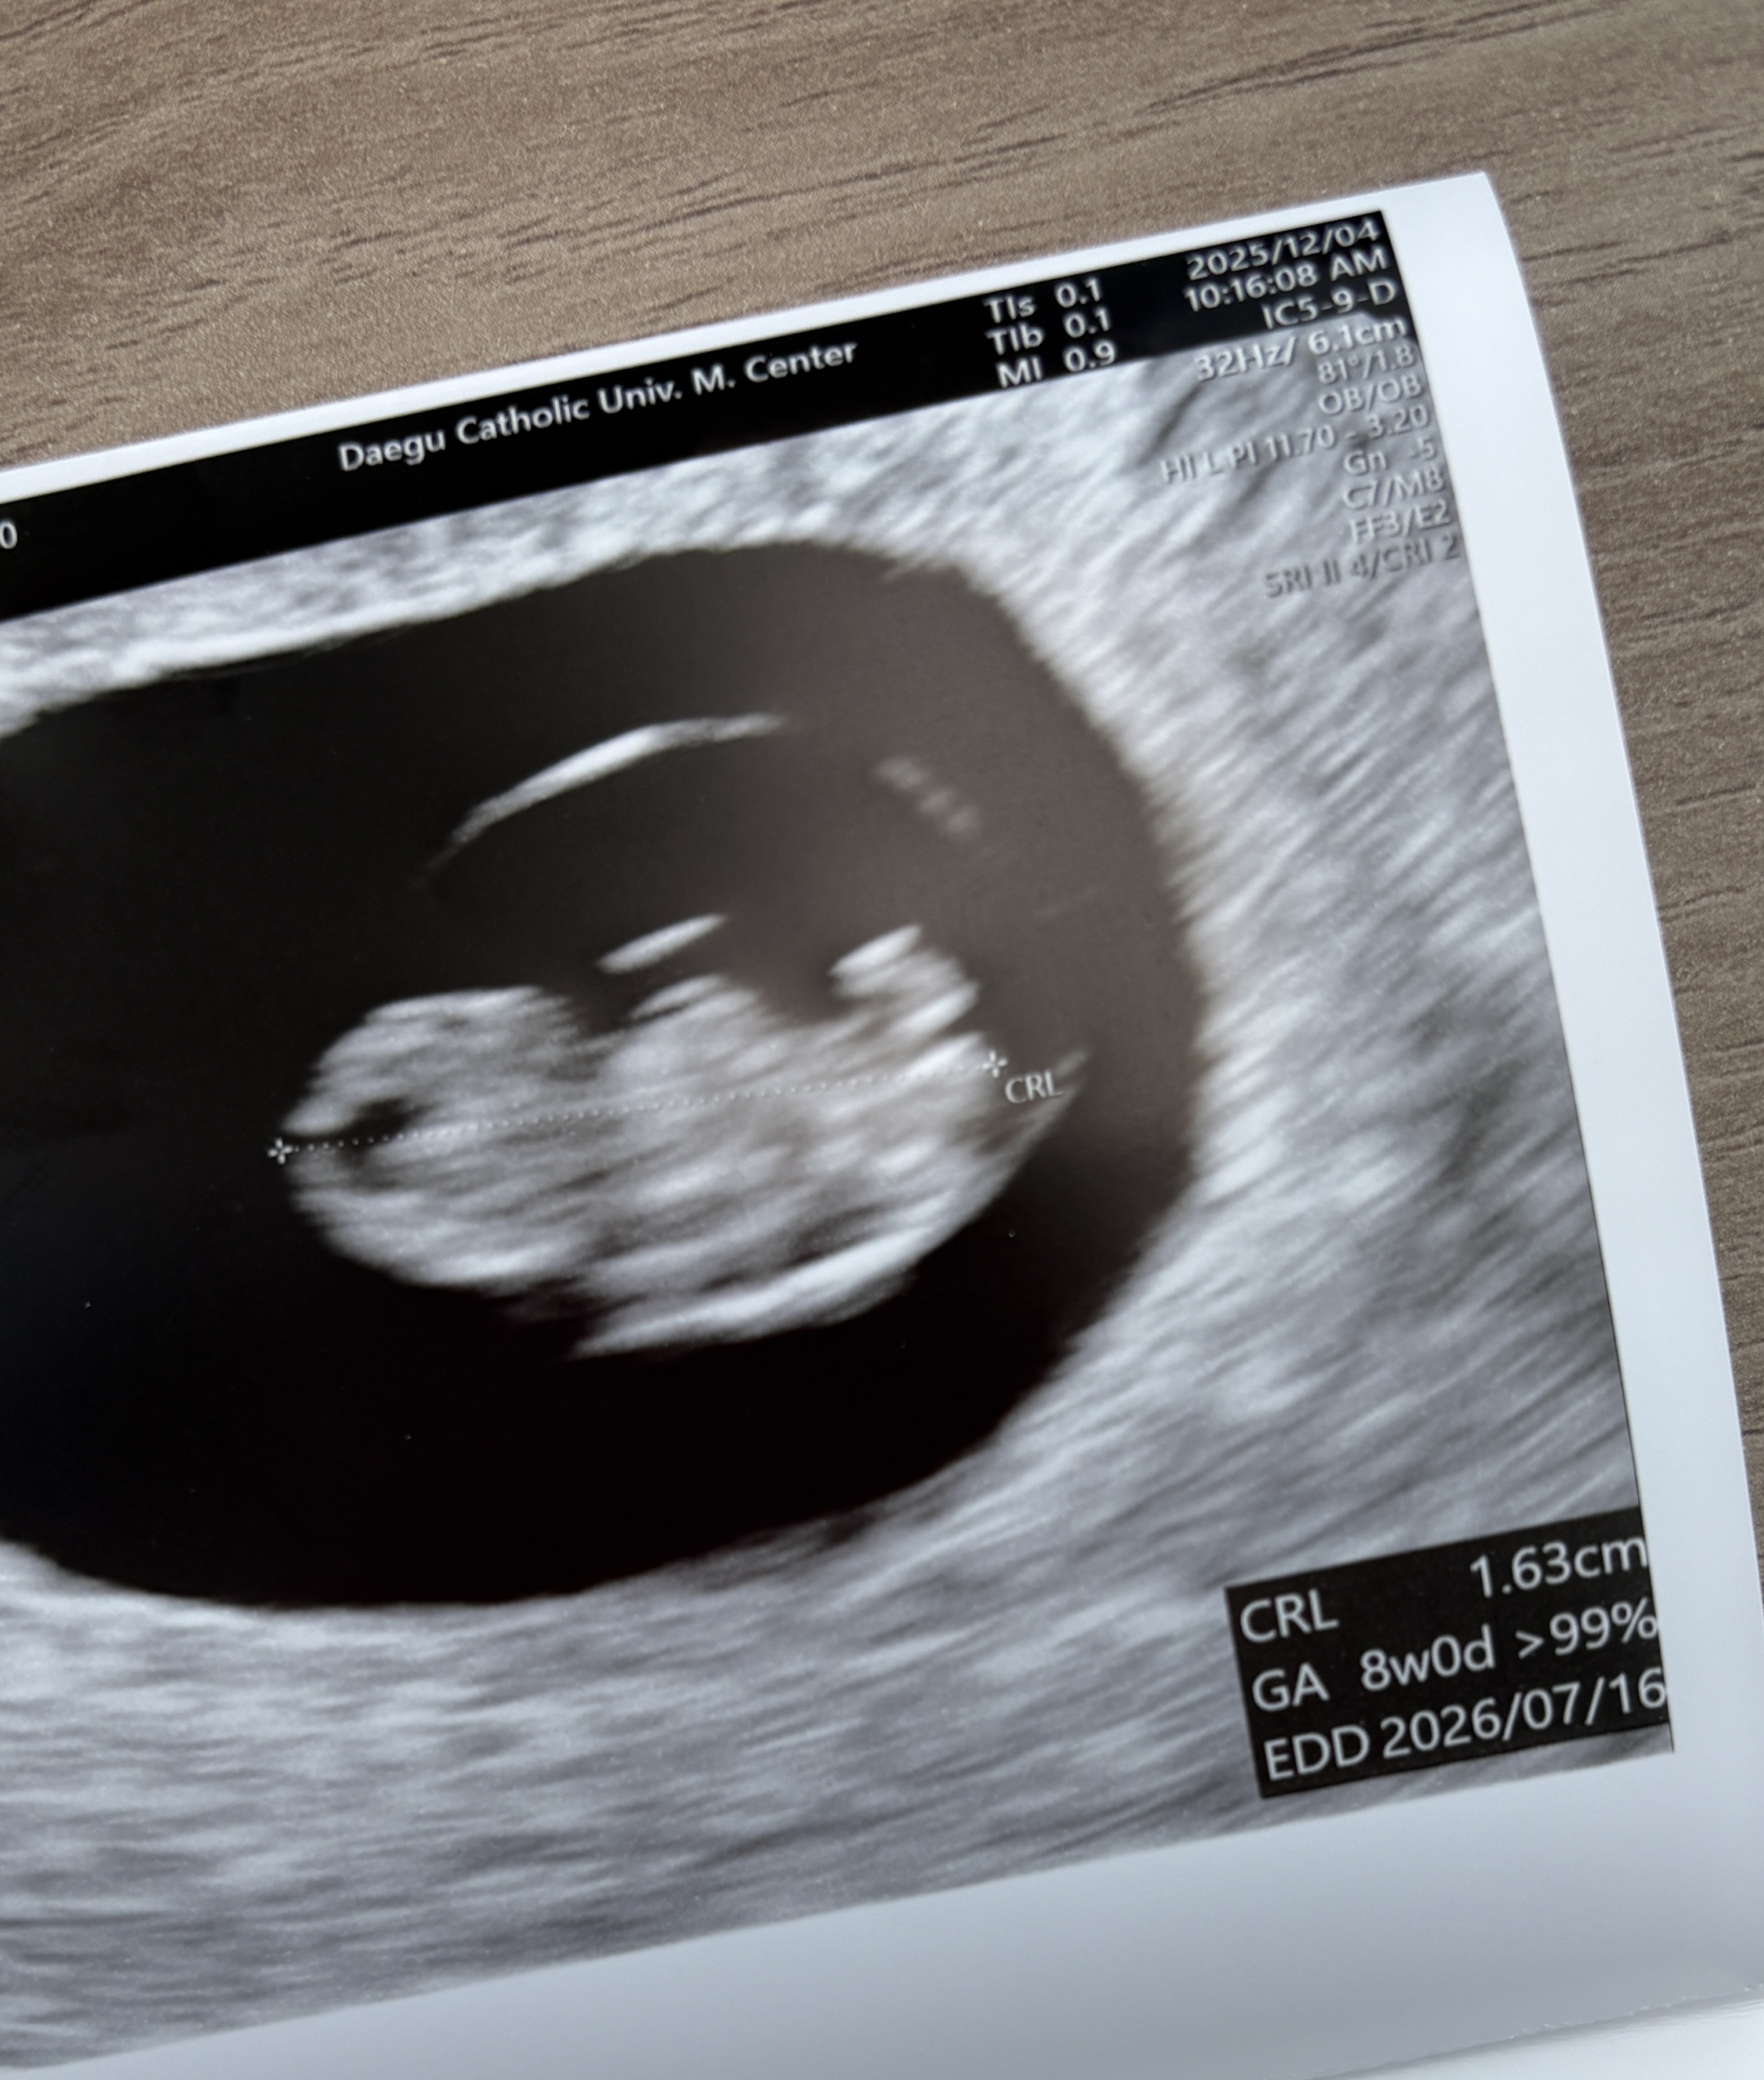

드디어 첫 심장소리를 듣고 왔어요~ 산전검사에서도 이상없고 일전에 한 유방 조직검사도 다행히 섬유선종에 석회가 있어 6개월마다 추적검사 소견 받았어요^^ 잘 있을까 걱정했는데 팔, 다리도 생기고 너무 신기해요 ㅋㅋㅋㅋㅋ 의사선생님도 초음파 보시더니 너무 귀여워~~~ 하고 육성으로 말씀 해 주셨네요 고작 1.6에 팔 다리라니 ㅠㅠ 보는순간 왜 눈물이 차오르는지 모르겠어요 ㅠㅠ 7주차인데 8주차 정도의 크기라고 키가 크고 심장도 안정적으로 잘 뛰고 있다고 하네요~ 안그래도 노산이라 자분 할지 제왕할지 생각중인데 여러분들 어떻게 하시나요? 그리고 각도법이랑 심장소리에 성별을 짐작할 수 있다고는 하는데 전 아무리 들어요 분간이 안되어요~ 빨리 성별이 궁금하긴 해요❤️